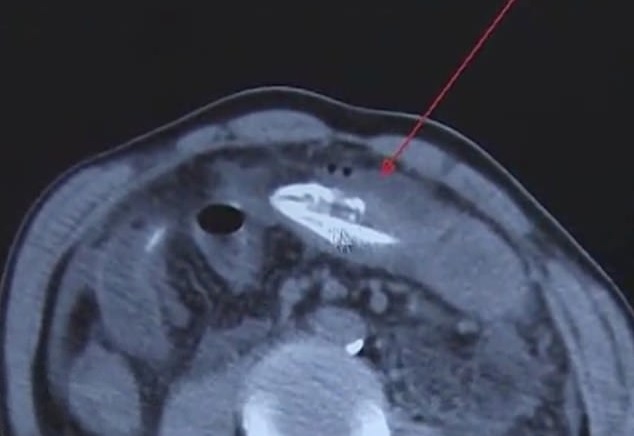

“We suspected that there was a foreign object in his abdominal cavity from a CT scan. But we couldn’t tell where it came from,” Huangjiang Hospital’s Dr. Li allegedly said.

During an emergency operation, the doctors were able to locate the eel, which was already dead at the time, and remove it from the patient’s abdomen.

“During the laparoscopy procedure, we detected that it was an eel. It had completely entered the abdominal cavity and already been dead,” the doctor added.